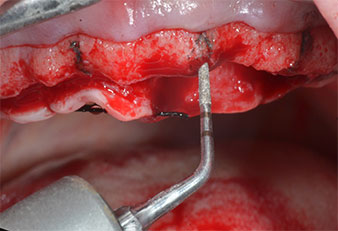

Para marcar las posiciones del implante y realizar la preparación piloto, se utilizó un inserto piezoeléctrico (Piezomed I1) con revestimiento de diamante y forma de llama (figura 3). Se tomaron precauciones para realizar movimientos hacia arriba y hacia abajo, con una potencia reducida, una irrigación completa y una baja presión (por debajo de 300 g). A continuación, se aplicó un inserto piloto (Piezomed I2A/I2P) para aumentar el diámetro inicial de 2 mm de los sitios de implante (figura 4), seguido de un inserto de 3 mm (Fig. 5).

Marcador ultrasónico Piezomed

Fig. 3: La preparación con inserto marcador ultrasónico Piezomed I1 se realizó con movimientos hacia arriba y hacia bajo, paralelos al eje longitudinal del área de trabajo.